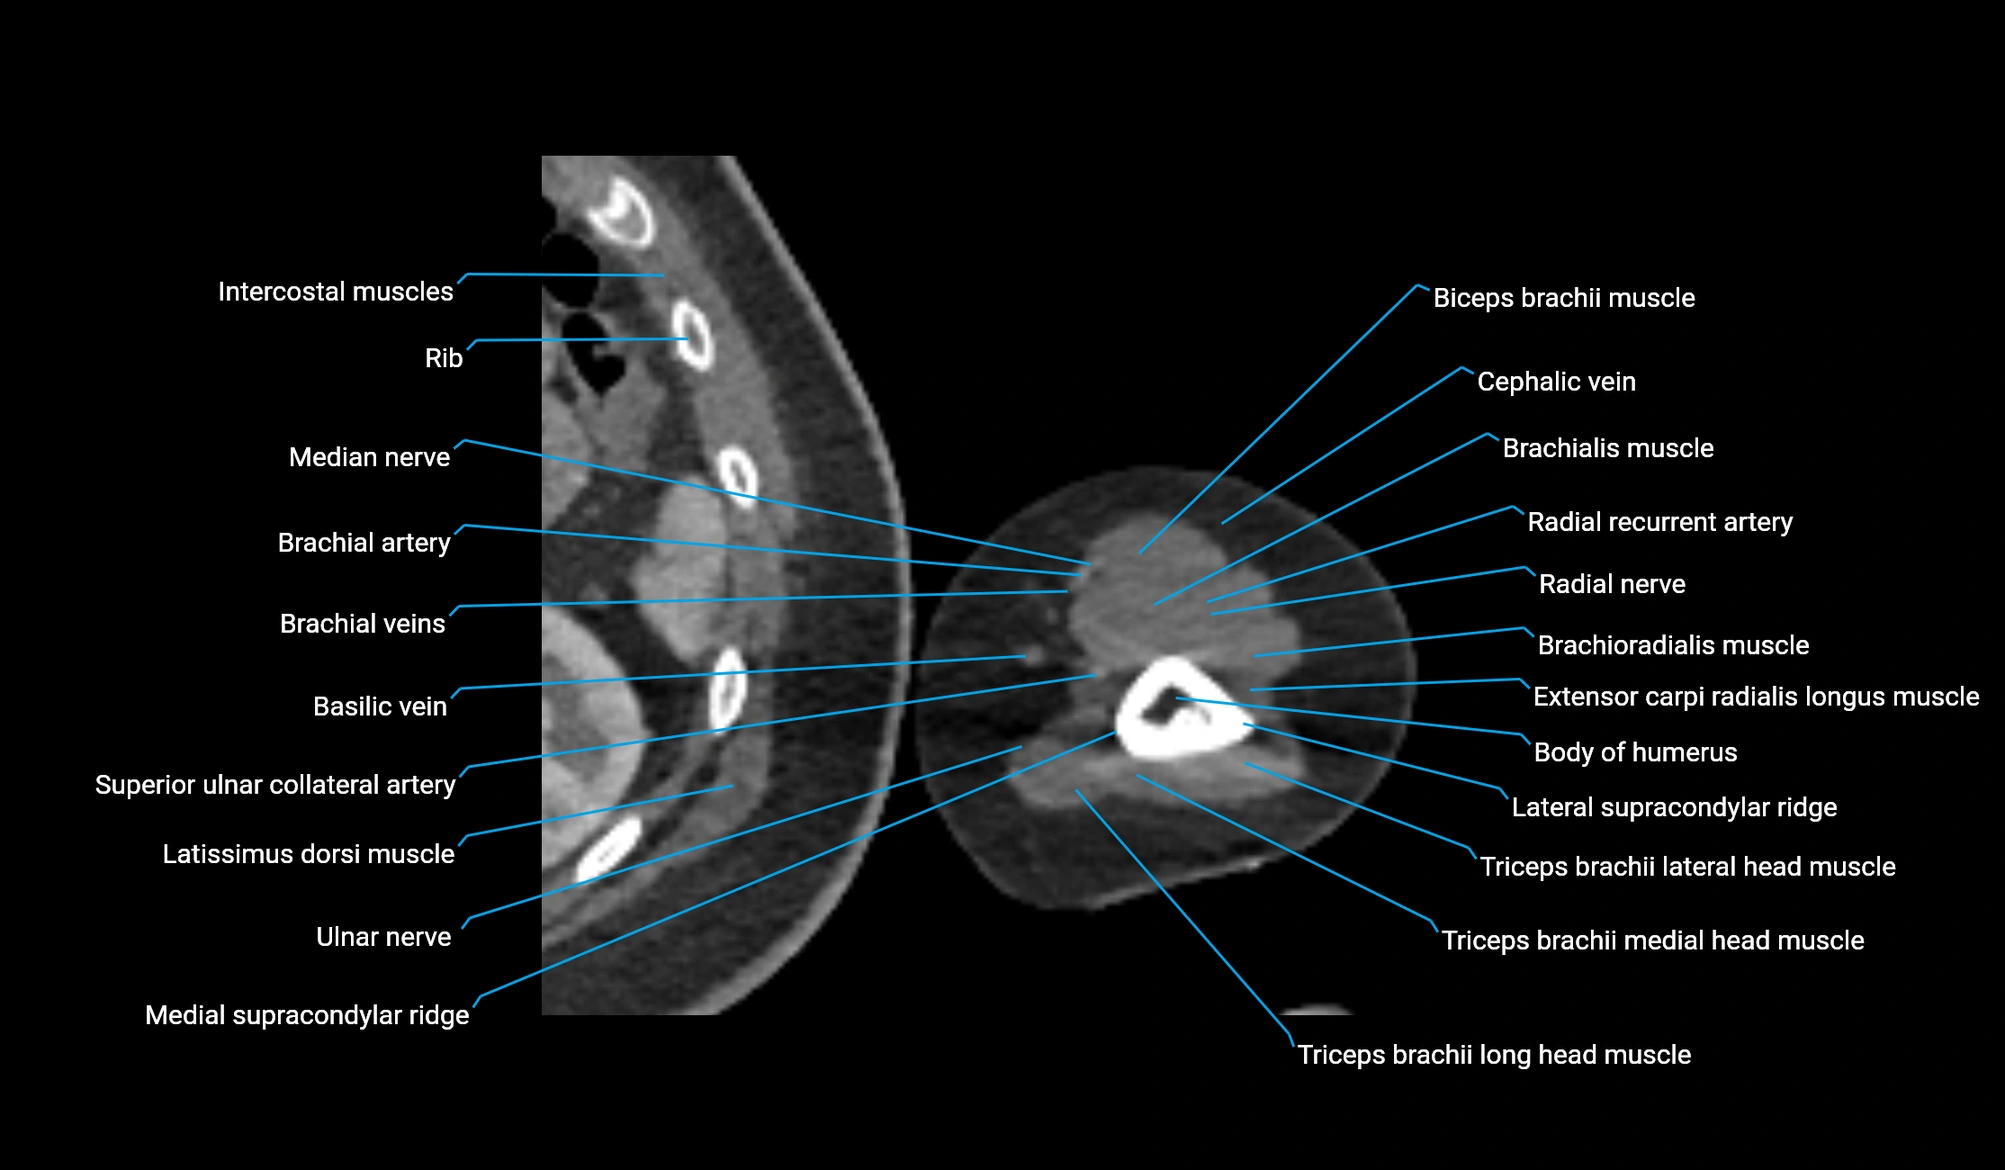

CT image